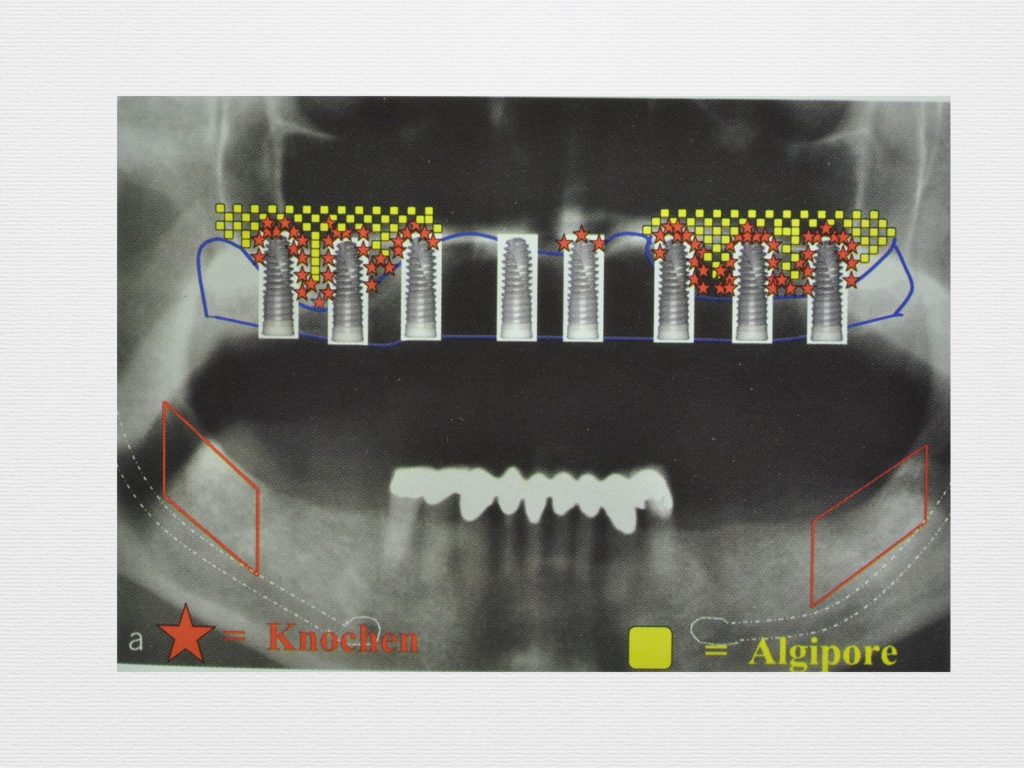

Принцип направленной костной регенерации. Костная регенерация под защитой мембраны Биоматрикс

Принцип направленной костной регенерации. Костная регенерация под защитой мембраны Биоматрикс

Принцип направленной костной регенерации. Костная регенерация под защитой мембраны Биоматрикс